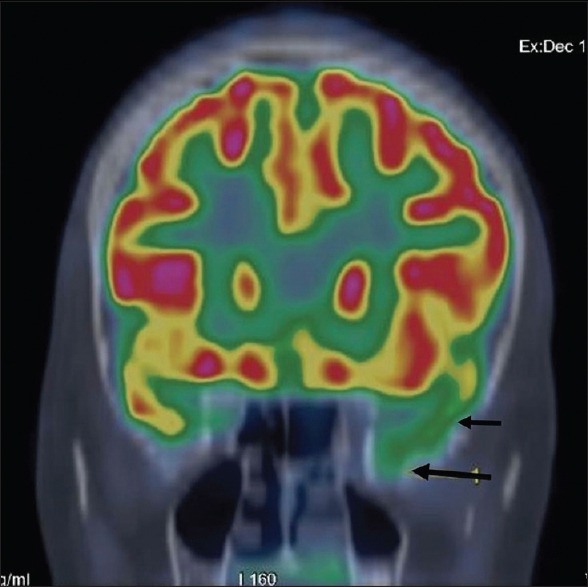

Abstract: In the present study patients with previously diagnosed MRI-negative temporal lobe epilepsy (TLE) on long-term video electroencephalography (VEEG) monitoring were re-evaluated with high resolution 3T MRI brain to look out for a skull base temporal lobe encephalocoele (TE). A total of 234 VEEGs were analyzed. TLE had been diagnosed in 104 patients based on semiology, ictal, interictal EEG data, and brain positron emission tomography (PET) studies. Of these, 99 patients had temporal lobe abnormality (78 had mesial temporal sclerosis, 8 had tumor, 3 had focal cortical dysplasia, and 10 had mixed pathology). Out of the five 1.5T MRI-negative TLE patients, two patients were diagnosed with TE on subsequent 3T MRI brain scans and one patient underwent electrocorticography-guided tailored resection for complete removal of epileptogenic tissue; with Engels class I seizure freedom at one year follow-up. We propose that TE should be carefully searched for, as a cause of refractory TLE, using high-resolution MRI sequences.